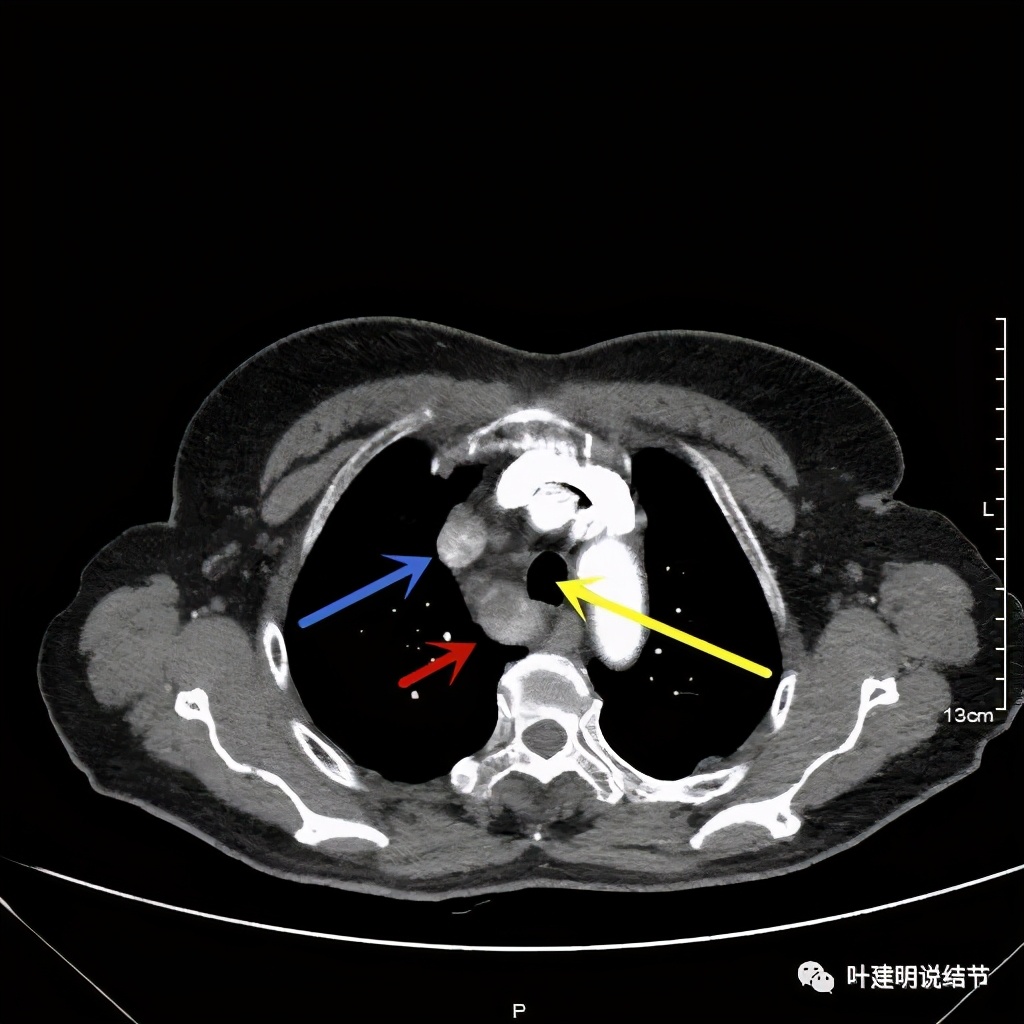

上图红色示肿瘤,黄色示气管,粉色示肿瘤与气管关系密切,桔色示左无名静脉,蓝色示上腔静脉,而且肿瘤密度不均杂乱